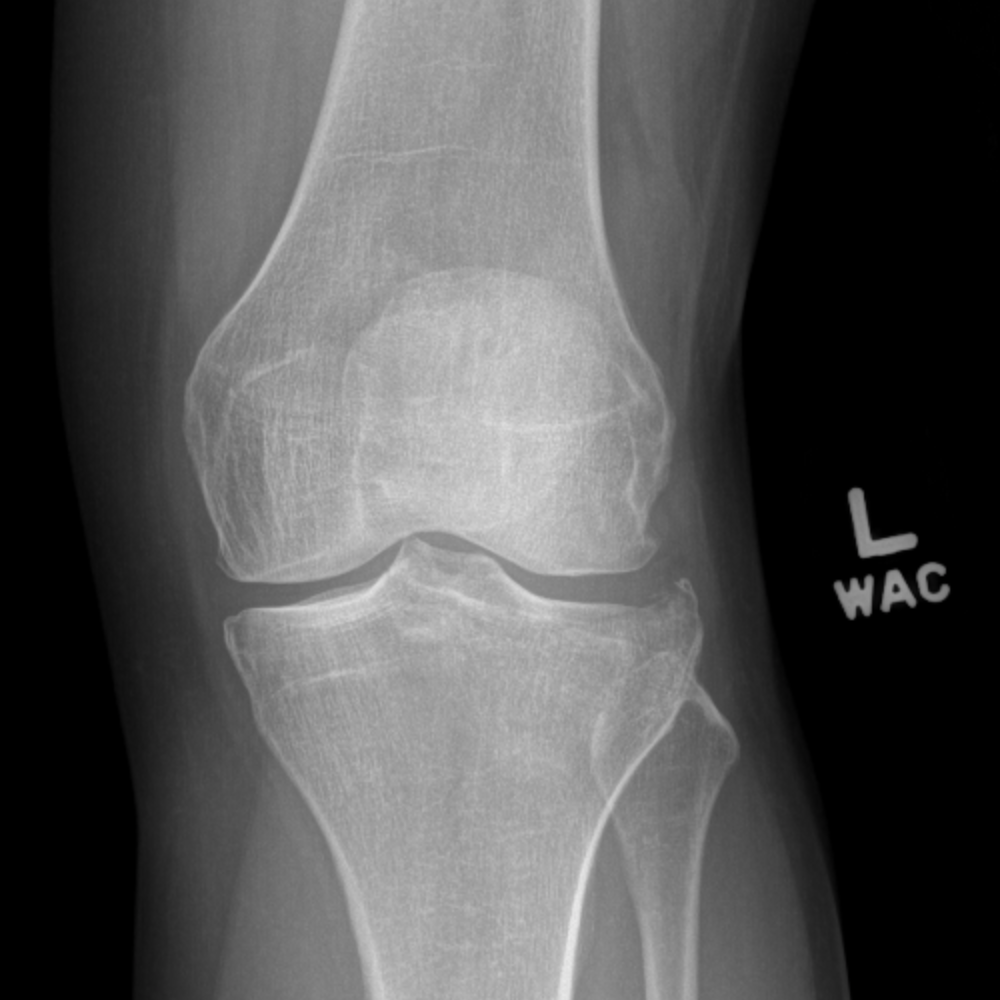

Inspect the skin circumferentially in order not to miss an open fracture. Social history – it’s important to know the pre-injury functional status and occupation of the patient, as well as smoking status. Past medical history – specifically ask about diabetes and peripheral vascular disease. These are commonly high-energy injuries – have a low threshold for an ATLS assessment and trauma call.Īlways perform an initial assessment for compartment syndrome, an open fracture and neurovascular status.ĭocument time and mechanism of injury in as much detail as you can – whether the fracture has occurred with a jumping injury, a twisting mechanism, or direct trauma (dashboard injury/contact sports) has implications on the likely associated soft tissue injuries.Īsk about pain elsewhere (distracting injury).Īsk about any sensory changes in the leg. Left to right: tibial plateau, shaft and pilon fractures Initial assessment The general principles of initial assessment and management are similar for all tibial fractures, so these will be dealt with together, with differences between the injuries highlighted where appropriate. As such, it is vital to consider neurovascular injury, soft tissue compromise and compartment syndrome in all tibial fractures. These fractures often result from high energy mechanisms, such as road traffic accidents (although they may also occur following low energy trauma, especially in those with osteoporotic bone). These injuries may coexist: it is relatively common to have a shaft fracture with intra-articular extension, or even separate fractures of the proximal/distal tibia and the shaft. Of note, the latter are distinct to ankle fractures, which do not involve the weight-bearing portion of the distal tibia (the plafond). In broad terms, fractures may be divided into those affecting the proximal tibial articular surface (tibial plateau fractures), extra-articular fractures of the shaft, and those affecting the distal articular surface (pilon fractures). The tibia is the most commonly fractured long bone. Admission, discharge and calling a senior